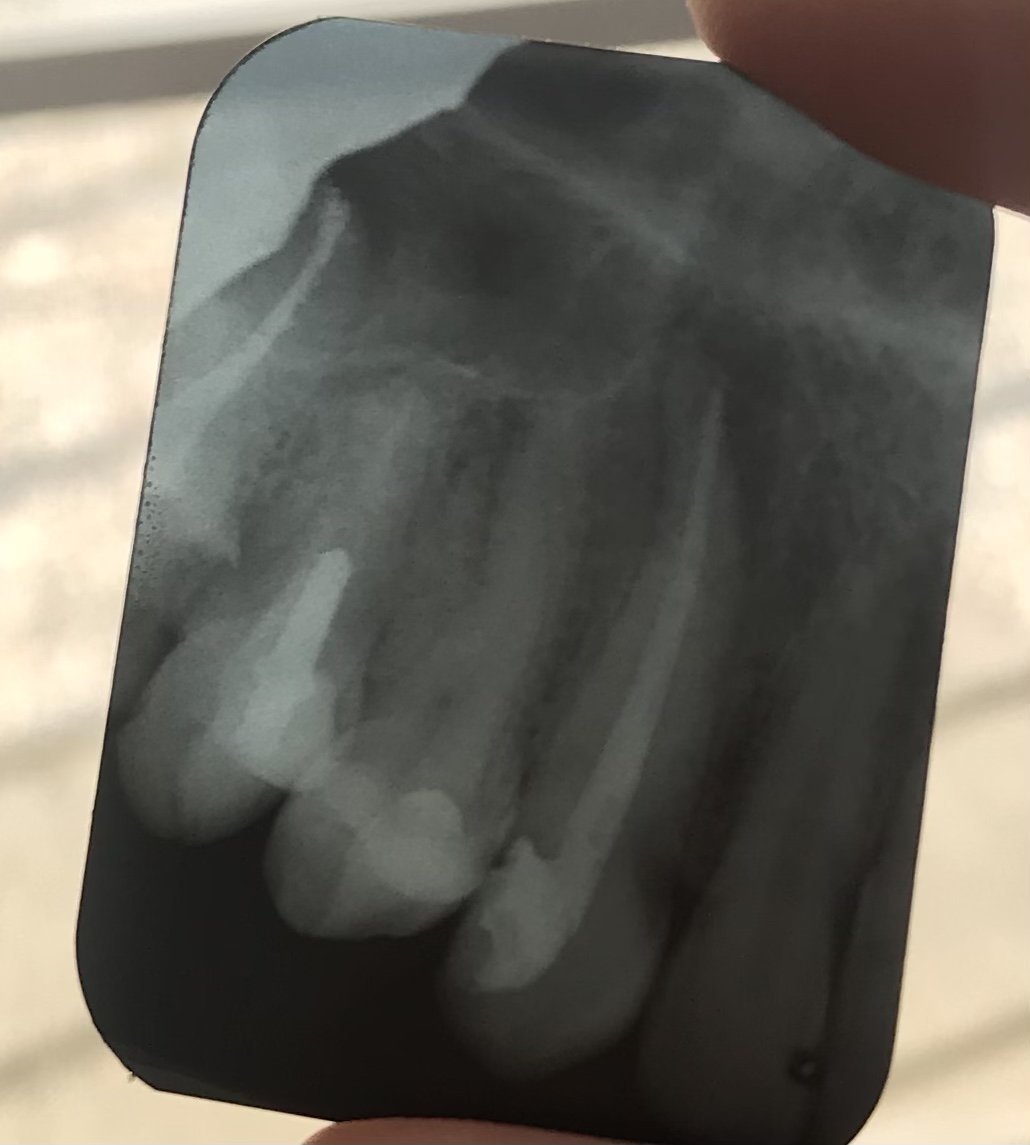

По-добре ли е да се постави имплант вместо кореново лечение и корона за умъртвен зъб?